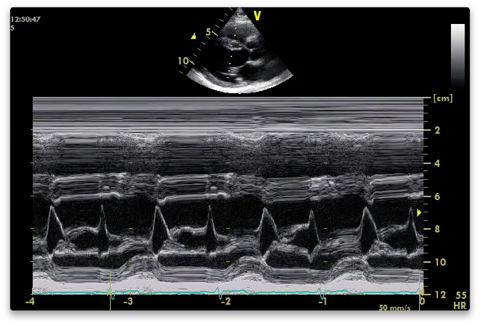

Through tips of mitral valve leaflets

- E point (valve tip at most anterior position in early diastole)

- Measure distance from E point to IVS (EPSS)

- A point where valve opens up again in late diastole with atrial systole